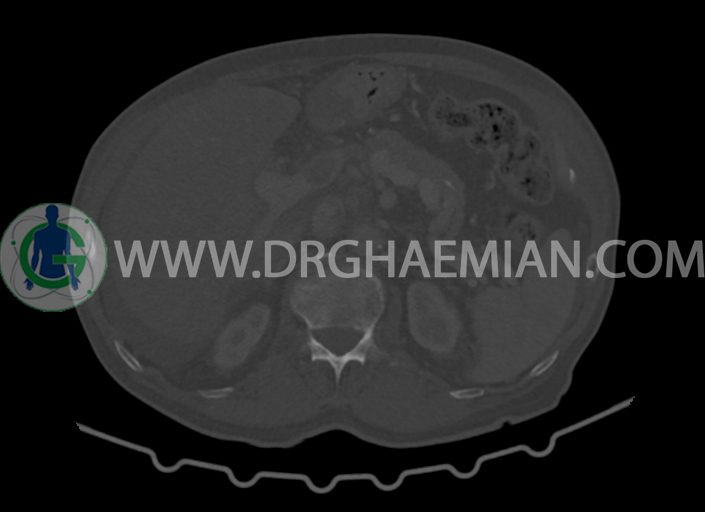

در سی تی اسکن اسپیرال شکم و لگن با کنتراست خوراکی و وریدی (مولتی دیدکتور 16 با مقاطع ظریف و بازسازی های ساژیتال و کرونال) :

–پروستات با دیامتر عرضی بزرگتر از نرمال 63mm همراه با بالجینگ به کف مثانه

-مایع آسیت با حجم Mild در ساب فرنیک دو طرف ، ساب هپاتیک و ساب اسپلنیک و اینترلوپ لگنپ

-مثانه با جدار ضخیم و نامنظم

-تغییرات DJD در مهره های لومبار

مشهود است.